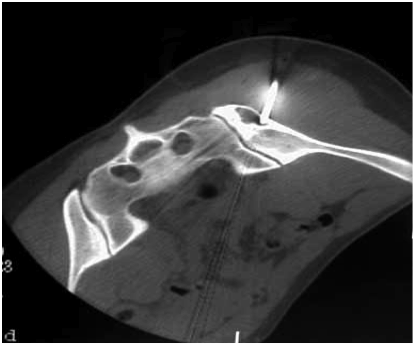

А.А. Жантурина, к.м.н. врач высшей категории Грыжа межпозвоночного диска – это дегенеративно-дистрофическое...